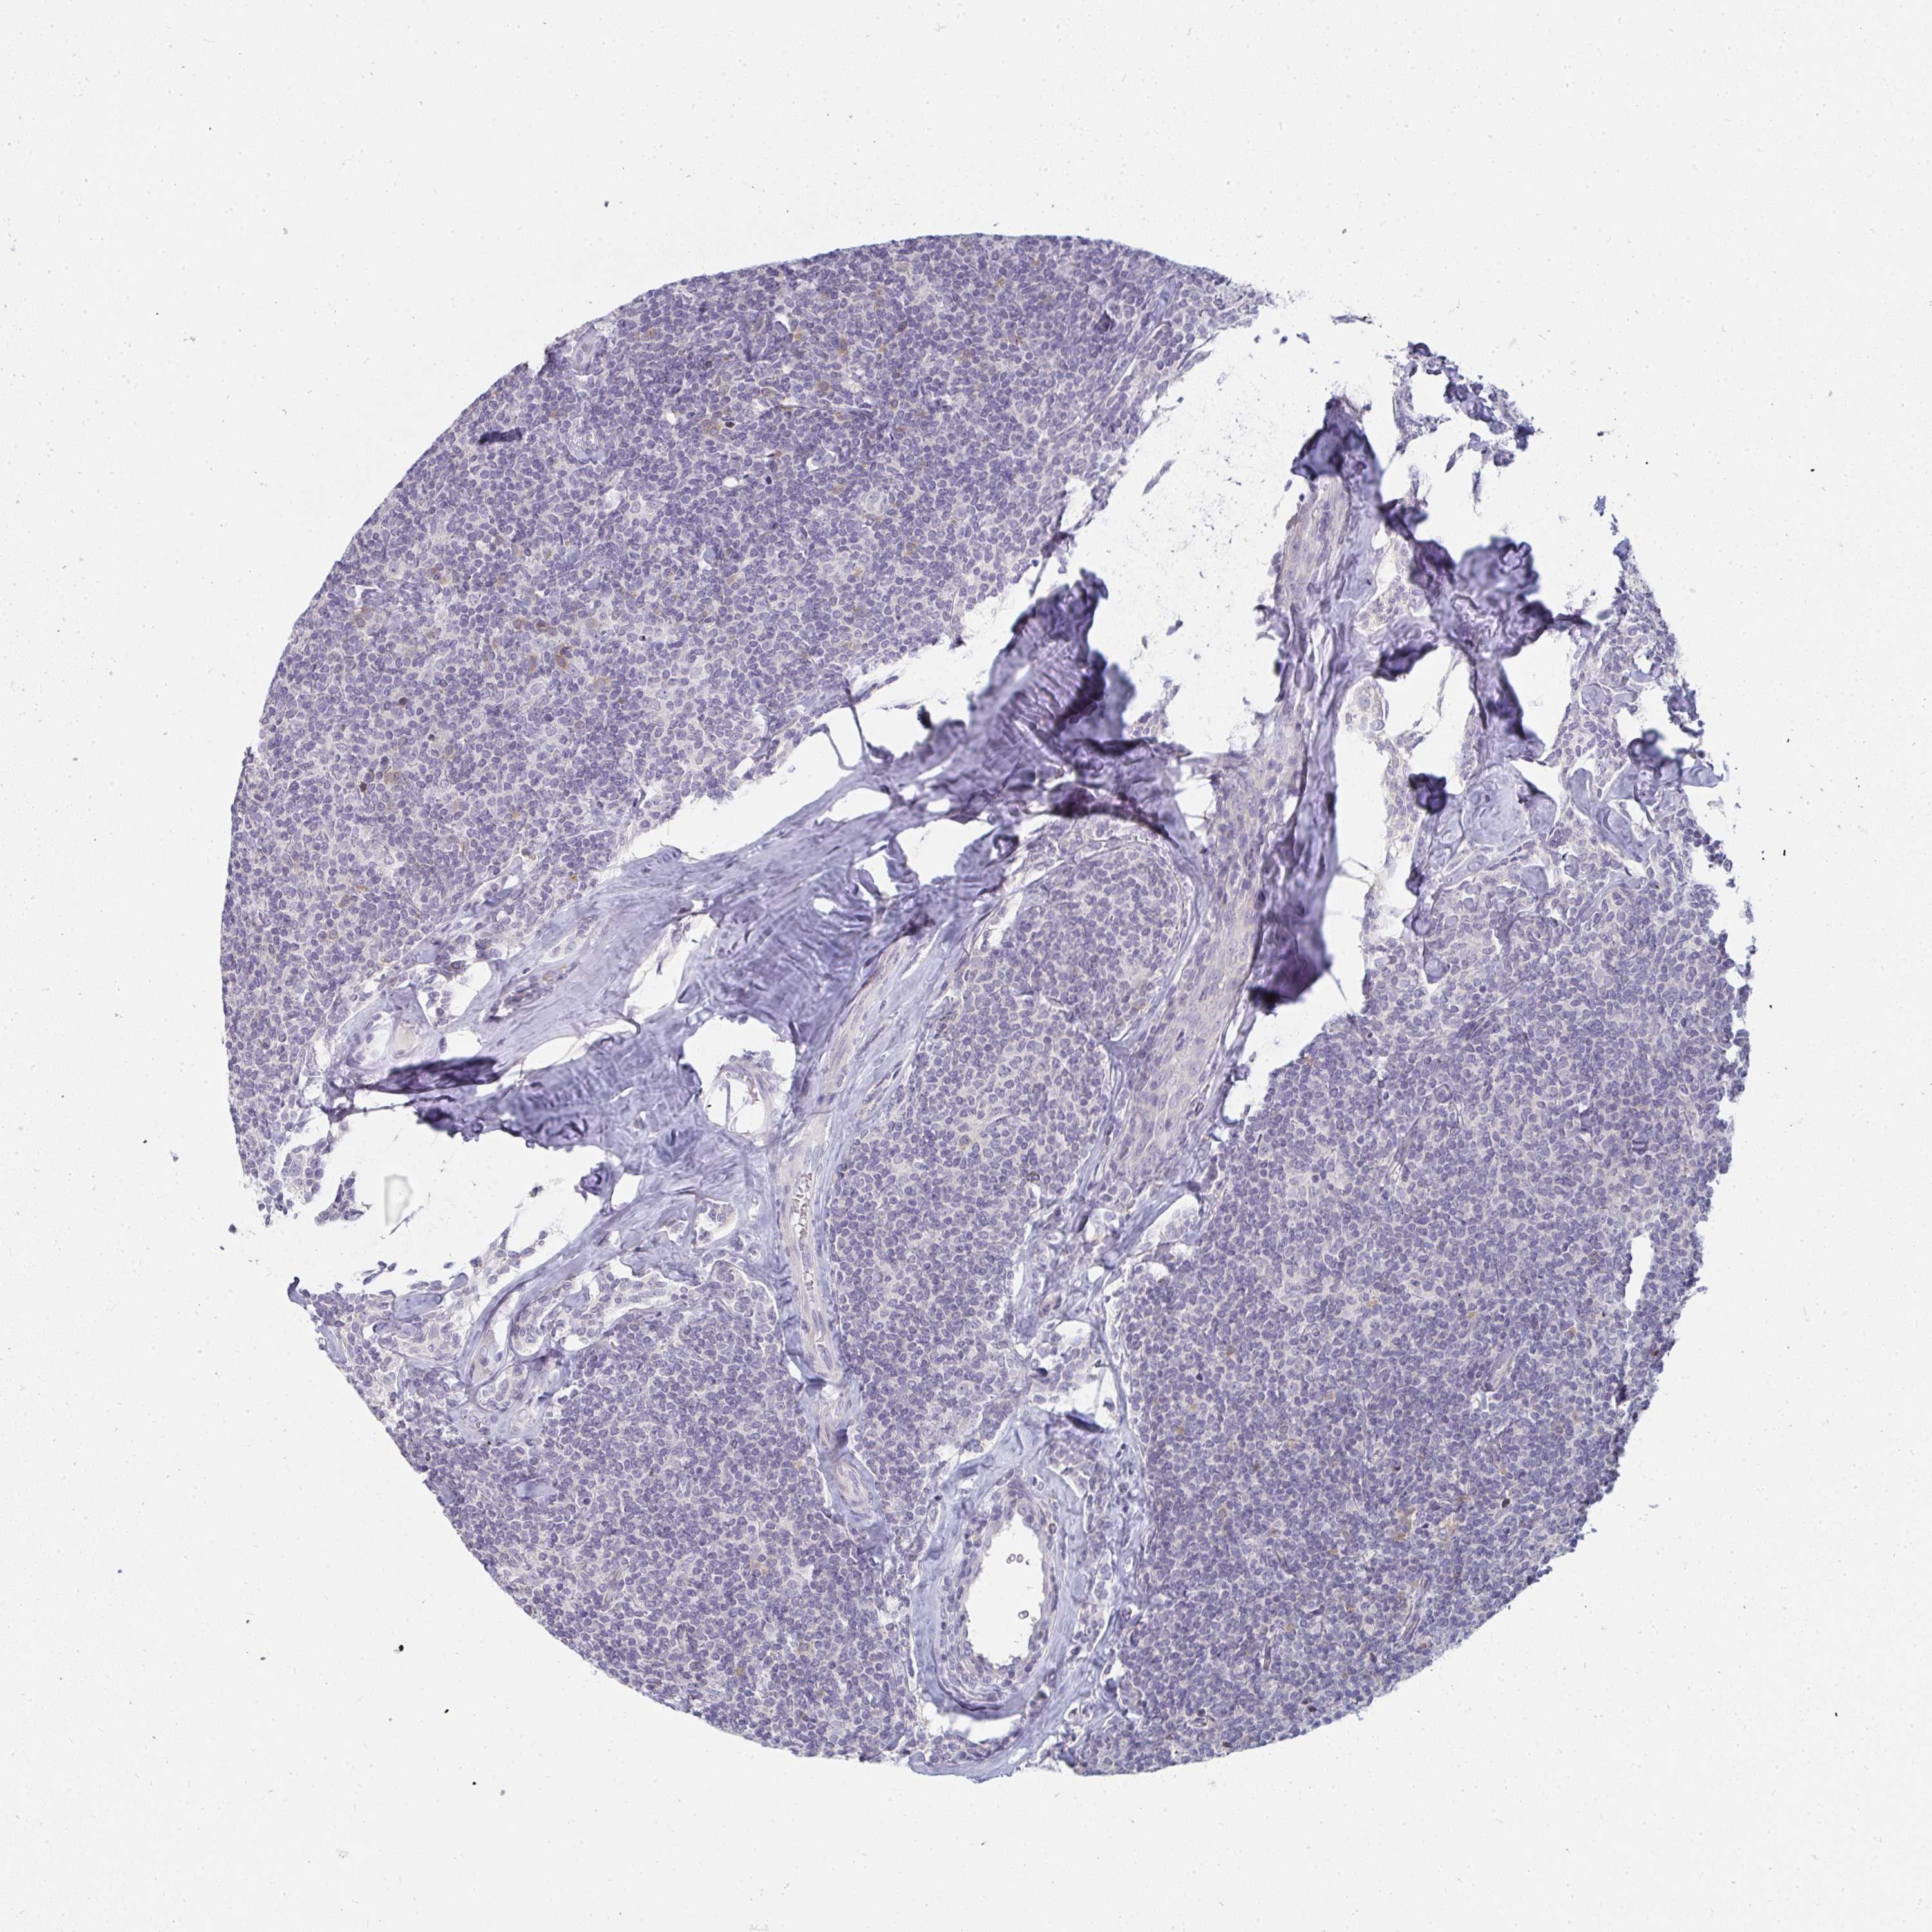

LYMPHOMA - Protein expressioni

A mouse-over function shows sample information and annotation data. Click on an image to view it in a full screen mode. Samples can be filtered based on level of antibody staining by selecting one or several of the following categories: high, medium, low and not detected. The assay and annotation is described here.

Antibody stainingi

Antibody staining in the annotated cell types in the current human tissue is reported as not detected, low, medium, or high, based on conventional immunohistochemistry profiling in selected tissues. This score is based on the combination of the staining intensity and fraction of stained cells.

Each image is clickable and will lead to virtual microscopy that enables deeper exploration of all samples and also displays staining intensity scores, fraction scores and subcellular localization as well as patient and tissue information for each sample.

Antibody HPA049911

Antibody CAB010161

Malignant lymphoma, non-Hodgkin's type, Low grade

Malignant lymphoma, non-Hodgkin's type, High grade

Hodgkin's disease, NOS